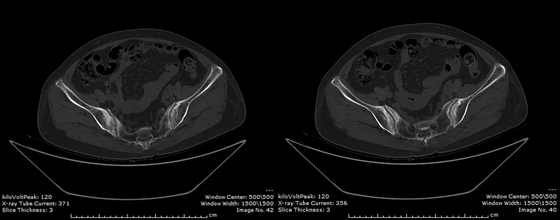

骶髂关节CT提示患者双侧骶髂关节面破坏及间隙狭窄

患者双侧骨盆X线提示骶髂关节异常